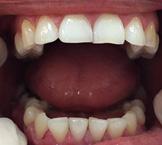

El tratamiento duró 1 año y 5 meses, se obtuvieron las relaciones molares y caninas, líneas medias coincidentes, adecuadas guías de desoclusion, overjet y overbite. Estudios extraorales finales: en la Figura 9 se ve la corrección de la mordida abierta anterior, mejoría en relación con la proporción del tercio medio e inferior de la cara, un perfil convexo.

Estudios intraorales finales

En las fotografías de la Figura 11 se muestran en la lateral derecha la clase I molar y canina bilateral, una correcta intercuspidación,las líneas medias dentales coincidentes, la corrección del overjet y overbite